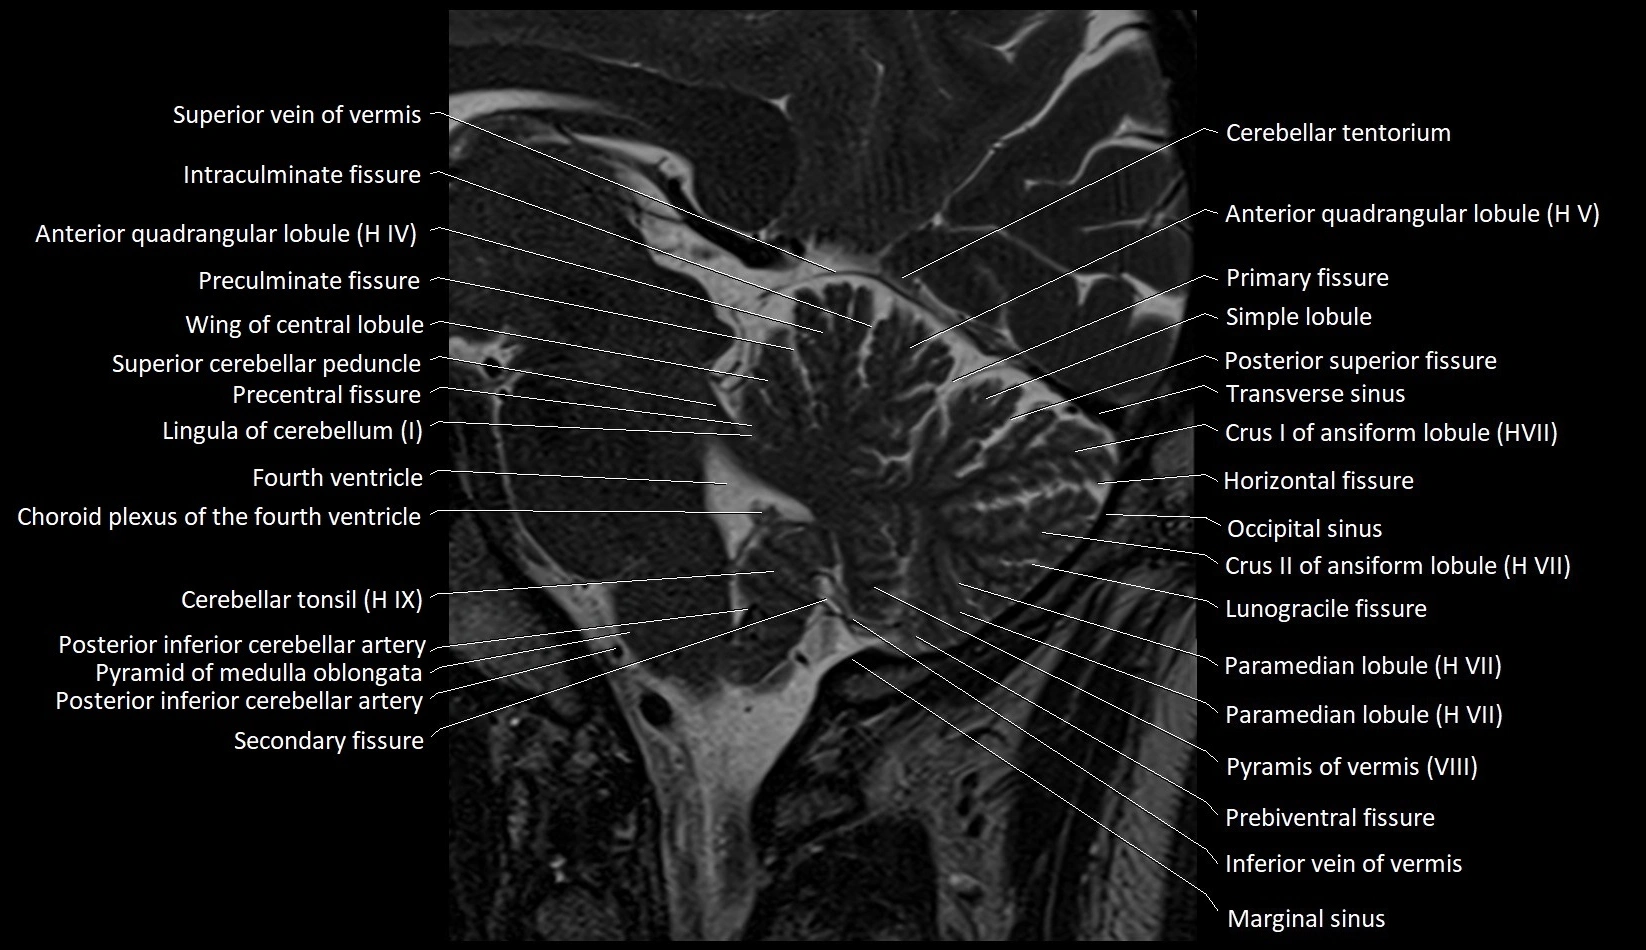

MRI images